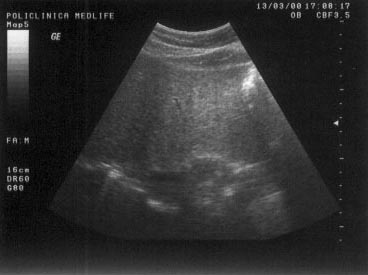

Imaginea hipoecogena

Invers, o structura care este mai putin reflectanta in comparatie cu mediul inconjurator se exprima, prin comparatie cu acesta sub forma unei structuri hipoecogene.

Imaginea hipoecogena apare mai neagra pe monitor decat structura cu care este comparata, fara sa fie complet transsonica.

Exemple:

rinichiul este mai hipoecogen fata de ficat;

abcese hepatice;

unele tumori hepatice.

Figura 9. In mod normal, parenchimul renal este mai hipoecogen decat perenchimul hepatic.

Figura 10. Imagine hipoecogena la limita corp-coada pancreas

Figura 11. Imagine hipoecogena la nivelul tiroidei

Figura 12. Imagine hipoecogena la nivelul sanului